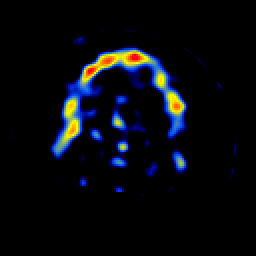

SPECT TL Study #8 -- Slice #46